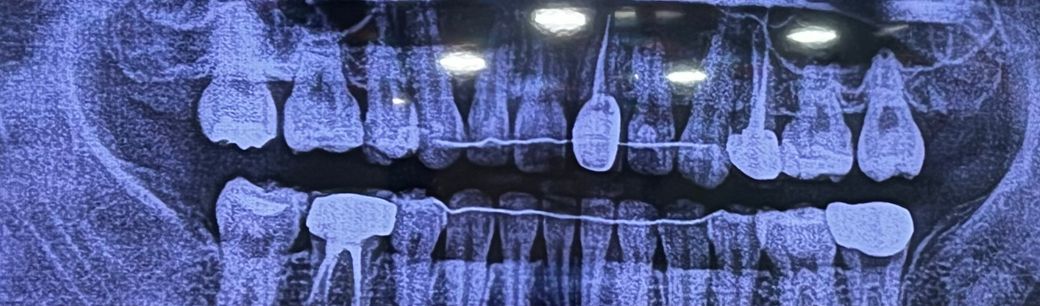

충치치료할게 있어보이나요???

어느 치과에서는 위에 크라운 하나 레진 두개 해야한다그러고

다른 치과는 정기검진만 하면서 보면 될 거 같다고 하셔서 궁금합니다ㅠㅠ

파노라마 사진만으로는 정확한 판단이 어렵습니다. 일단 화질 자체도 좋지 않고 파노라마는 3차원적인 구강 구조를 2차원적으로 표현 한 것이므로 왜곡이 상당합니다. 따라서 참고용이며 시진과 촉진 그리고 여러가지 검사를 같이해서 판단해야 합니다.

파노라마 상에서는 간단한 충치는 볼수가 없습니다. 아마도 레진이나 지켜보자고 한건 충치가 크지 않은거니 직접 육안으로 봐야 알수 잇을것같습니다.

화질이 지나치게 낮고 파노라마 사진으로는 충치 진단을 내리기가 힘듭니다. 치근단 사진을 올리시면 더 도움을 드릴수있습니다